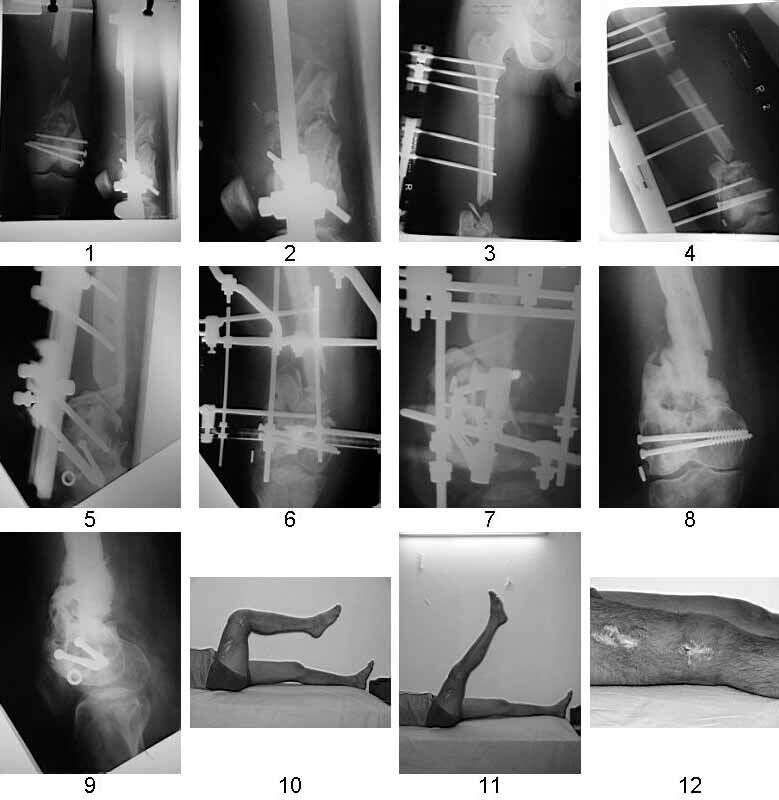

Similar case.

They do well with bone transport.

I do an acute or accelerated shortening to reduce the gap as much as proximal, and distract proximally to restore length.

In this particular case, notice the change of fixator - orthofix type of unilateral fixator worked well initially but did not allow me to compress beyond a point, which is when I changed to an ilizarov for further compression at the gap/nonunion site.